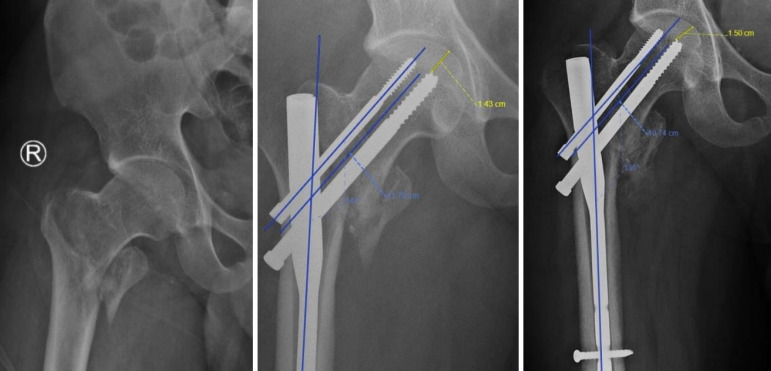

Methods: Geriatric patients who presented with AO/OTA 31A1 and 31A2 femur fractures and treated with proximal femoral nailing between July 2021 and June 2023 were include in this prospective cohort study. Based on the degree of MCR, they were divided into positive, neutral, or negative MCR groups. The demographic baseline characteristics, postoperative radiographic femoral neck-shaft angle and neck length were analyzed at 6, 12 and 24 weeks post-surgery. Functional outcomes such as modified Harris Hip Score (HHS) and time to full-weight bearing were also analyzed.

Results: 47 patients (Male: Famale 35:12) with mean age of 65.8 ± 4.2 years were included in this study. Twenty-two cases had neutral support, nine had negative support, and sixteen had positive support in the medial cortex post-operatively. Baseline characteristics of the three groups were comparable. No significant differences were found in the femur neck length and femur neck-shaft angle changes post-surgery between the groups. The modified HHS was not found to be significant between the groups (P = 0.883) as that of the time to full weight bearing (P = 0.789).

Conclusion: The type of reduction achieved based on medial cortical alignment does not affect the femur neck length shortening or varus collapse. Future randomized controlled trials are needed to validate the findings noted in the study.